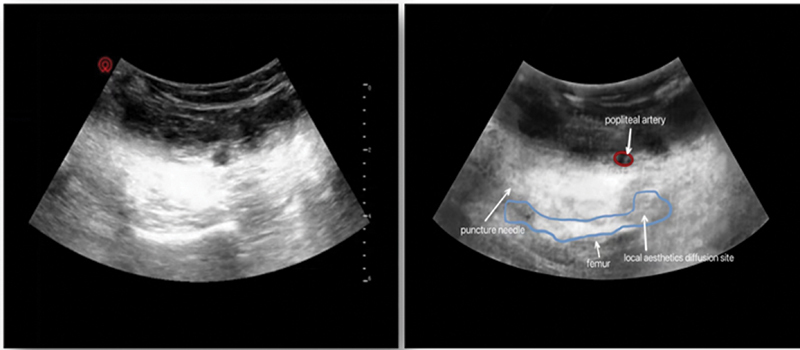

我们的目的是比较腘动脉与膝关节后囊间间歇多次浸润(IPACK)联合内收管阻滞(ACB)和单独间歇ACB对屈曲挛缩性膝关节炎患者行全膝关节置换术(TKA)的镇痛效果。将46例选择性单侧TKA患者分为间歇多次IPACK联合ACB组(IA组)和间歇多次ACB组(A组),每组ACB用0.375%罗哌卡因20 mL, IA组IPACK用0.25%罗哌卡因20 mL。术后第1天[POD1]和术后第2天[POD2]上午7:30 ~ 8:30采用间歇性多重神经阻滞进行术后镇痛(IPACK阻滞联合ACB组为IA组,ACB组为A组)。评估的主要结果是休息时疼痛、运动诱发疼痛(MEP)和POD1和POD2的活动范围(ROM)。次要结局包括阿片类药物消耗、首次下床时间、下床距离和术后并发症。我们观察到,与A组相比,IA组MEP降低,ROM变宽,行走距离变长,阿片类药物消耗减少。其他结果要么组间相似,要么临床差异不显著。我们得出结论,在屈曲挛缩性膝关节炎患者行TKA时,多次间歇性IPACK联合ACB治疗比单独多次间歇性ACB治疗提供更好的镇痛效果。

We aimed to compare the analgesic effects of intermittent multiple infiltrations between the popliteal artery and capsule of the posterior knee (IPACK) combined with adductor canal block (ACB) and intermittent ACB alone in patients with flexion contracture knee arthritis undergoing total knee arthroplasty (TKA). Forty-six patients who underwent elective unilateral TKA were divided into two groups (n = 23 each): intermittent multiple IPACK combined with ACB (group IA) and intermittent multiple ACB (group A). ACB was performed with 20 mL of 0.375% ropivacaine in each group and IPACK with 20 mL of 0.25% ropivacaine in group IA. Intermittent multiple nerve blocks were used for postoperative analgesia (IPACK block combined with ACB in group IA and ACB in group A between 7:30 and 8:30 a.m. on postoperative day 1 [POD1] and postoperative day 2 [POD2]). Primary outcomes assessed were pain at rest, motion-evoked pain (MEP), and range of motion (ROM) on POD1 and POD2. Secondary outcomes included opioid consumption, first ambulation time, ambulation distance, and postoperative complications. We observed that compared with group A, MEP decreased, ROM became wider, ambulation distance was longer, and opioid consumption decreased in group IA. Other outcomes were either similar between the groups or showed clinically insignificant differences. We conclude that multiple intermittent IPACK therapy combined with ACB provides superior analgesia than multiple intermittent ACB therapy alone in patients with flexion contracture knee arthritis undergoing TKA.